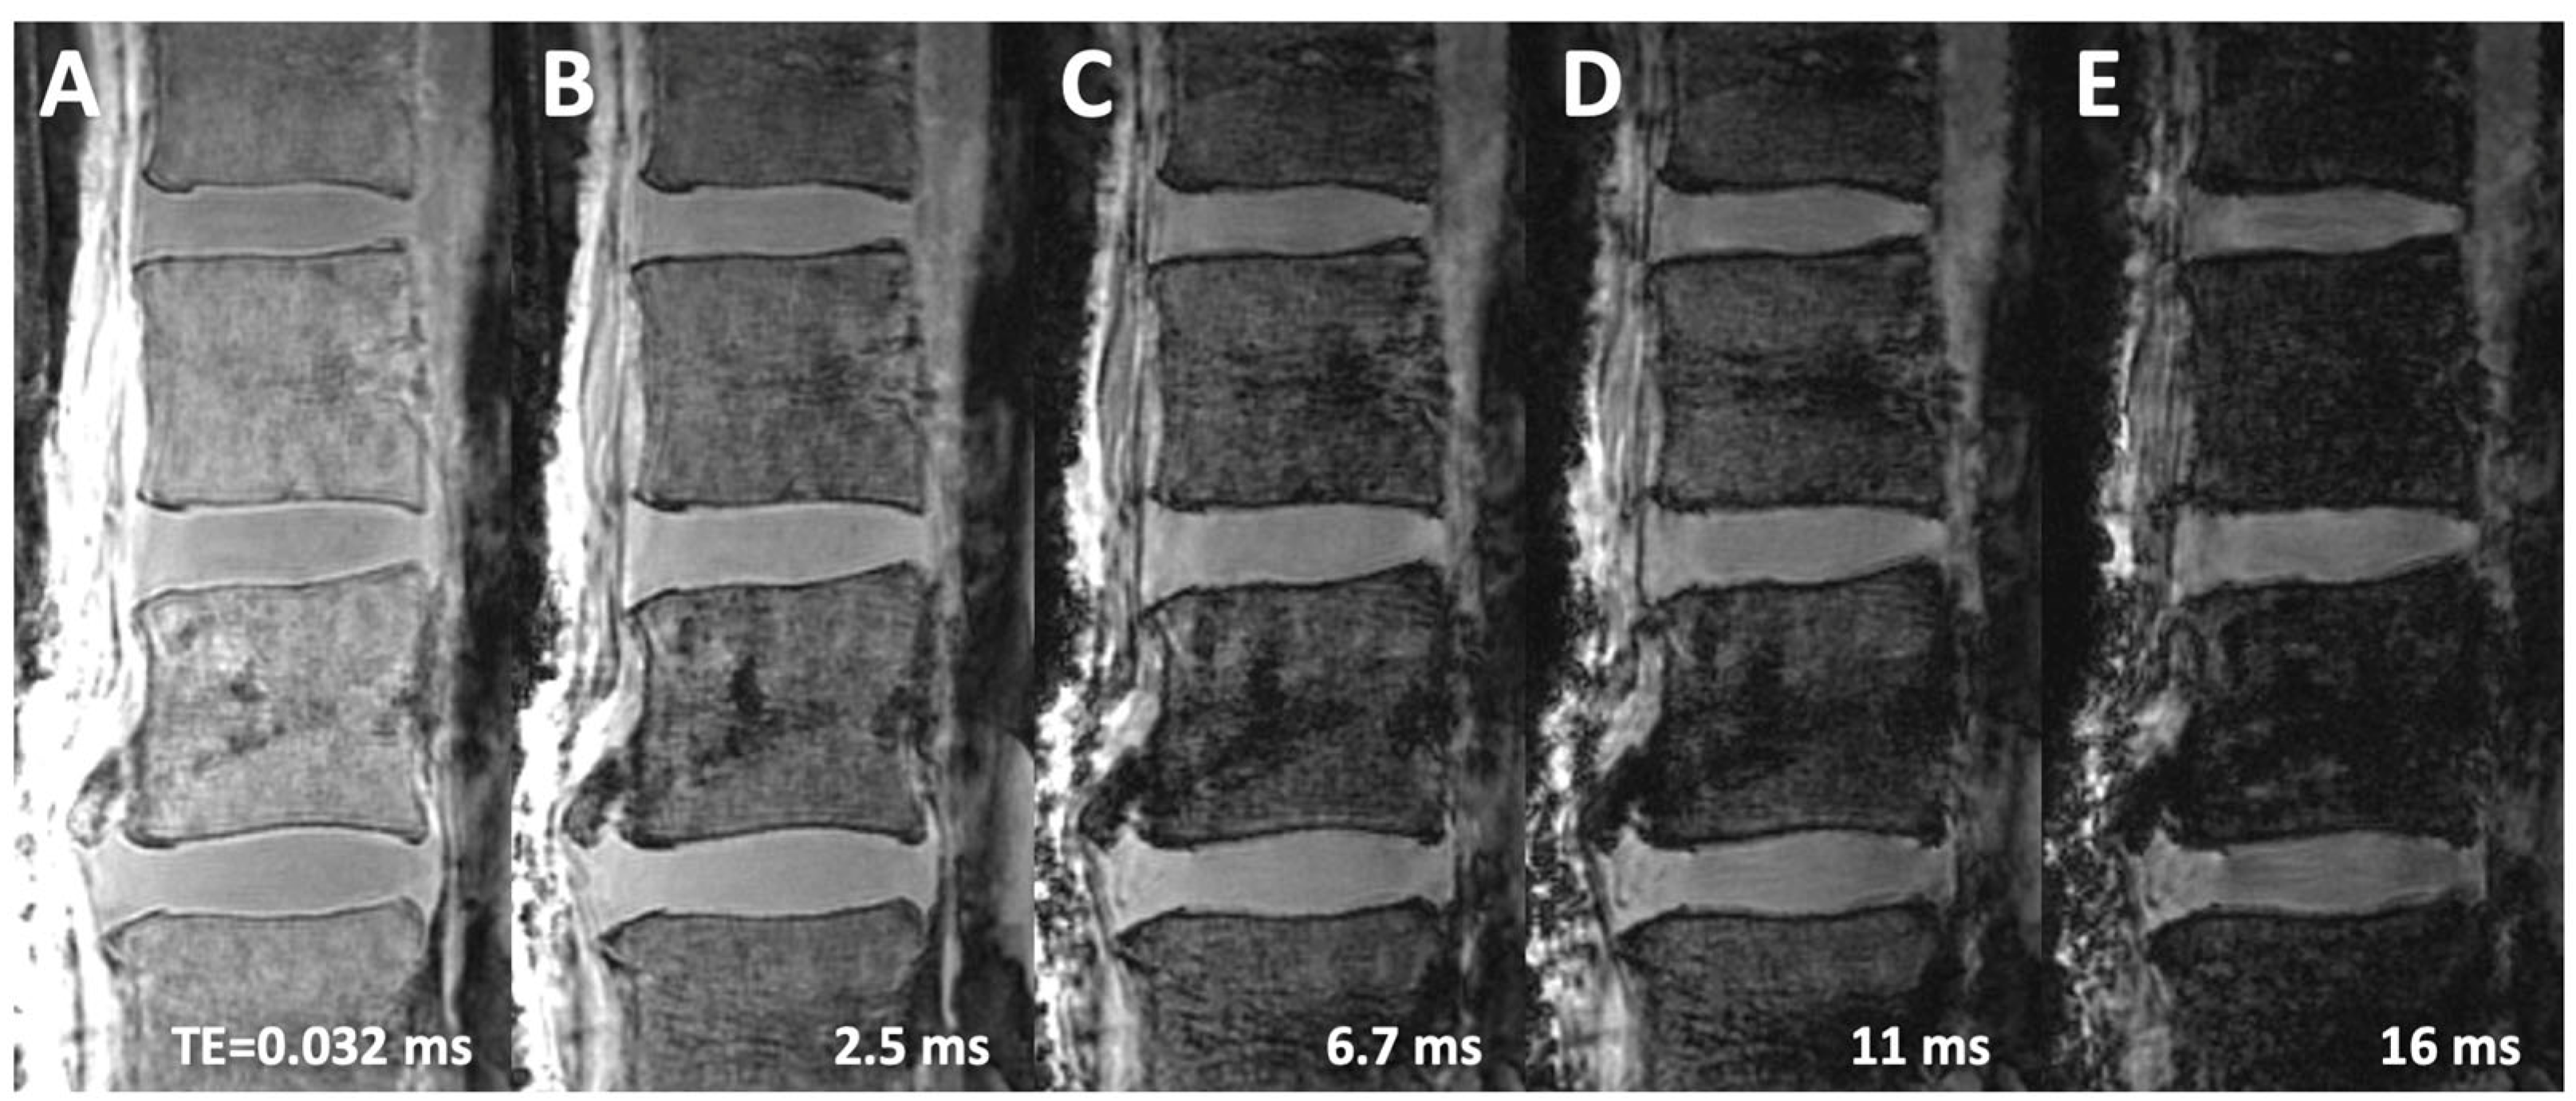

| 3D Cones | 50 | 0.03 | 16.7 (3.6) | 15.0 (1.1) | 10.4 (2.2) | 1.8 (3.4) | 6.3 (1.8) |

| 50 | 2.5 | 13.7 (3.2) | 14.6 (0.8) | 5.7 (1.6) | −0.8 (3.2) | 8.0 (2.2) | |

| 50 | 7 | 9.2 (2.1) | 12.7 (0.8) | 3.0 (0.8) | −3.4 (2.7) | 6.2 (1.5) | |

| 50 | 16 | 5.4 (0.9) | 10.3 (0.9) | 1.8 (0.2) | −4.8 (1.8) | 3.6 (0.9) | |